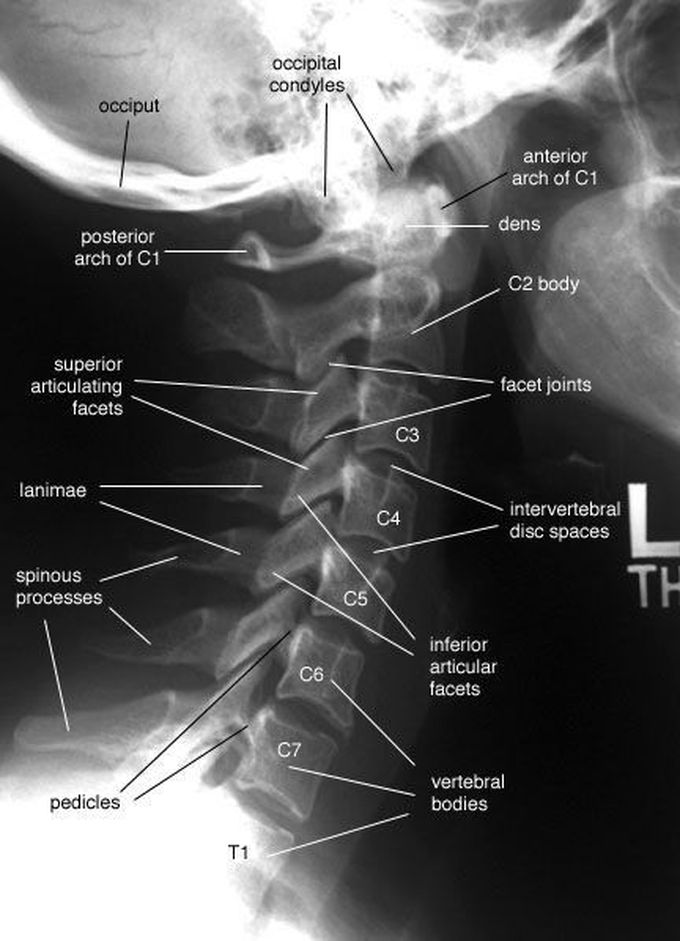

Cervical Xray Labeled . This article will show you. An article on radiopaedia.org discussing the cervical spine series, a radiological reference for the upper part of the spine. This online presentation reviews a variety of cervical spine entities, with case examples and illustrations to clarify concepts, and discusses differential considerations and potential diagnostic pitfalls. At the time the article was last revised arlene campos had no financial relationships to ineligible companies to. The cervical vertebrae should align correctly, forming a.

Cervical Vertebrae Lateral View Labeled